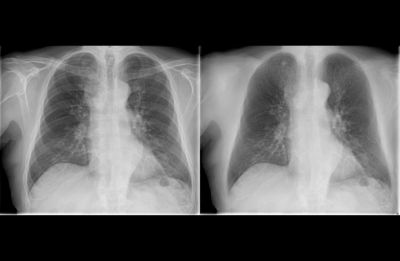

Philips Bone Suppression image enhancement technology uses AI to suppress bones on digital adult erect chest X-ray images, creating both a conventional image and an unobstructed soft tissue image with a single exposure. Bone Suppression is fully integrated into the Eleva workflow.

Clinical Image of Bone Suppression

By providing a soft tissue image in addition to a conventional chest image, Bone Suppression provides decision-making support without the need for additional X-ray dose or time. With Bone Suppression, actionable lung nodule detection is improved up to 16.8%. [1]